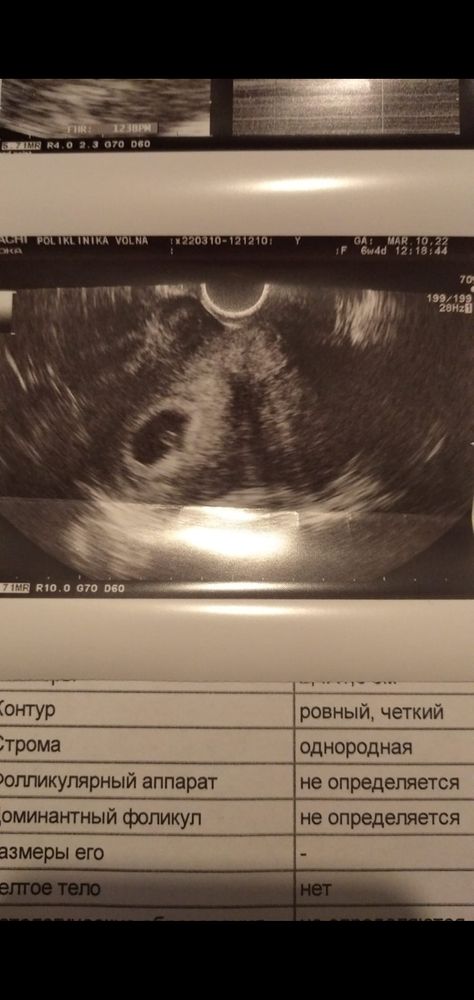

Евгения , у вас по рамзи - девочка, но опять таки, это просто баловство. Можете после 9 недель сделать анализ крови на пол, что б знать быстрее. Я делала нипт и уже на 11 неделе знала пол.